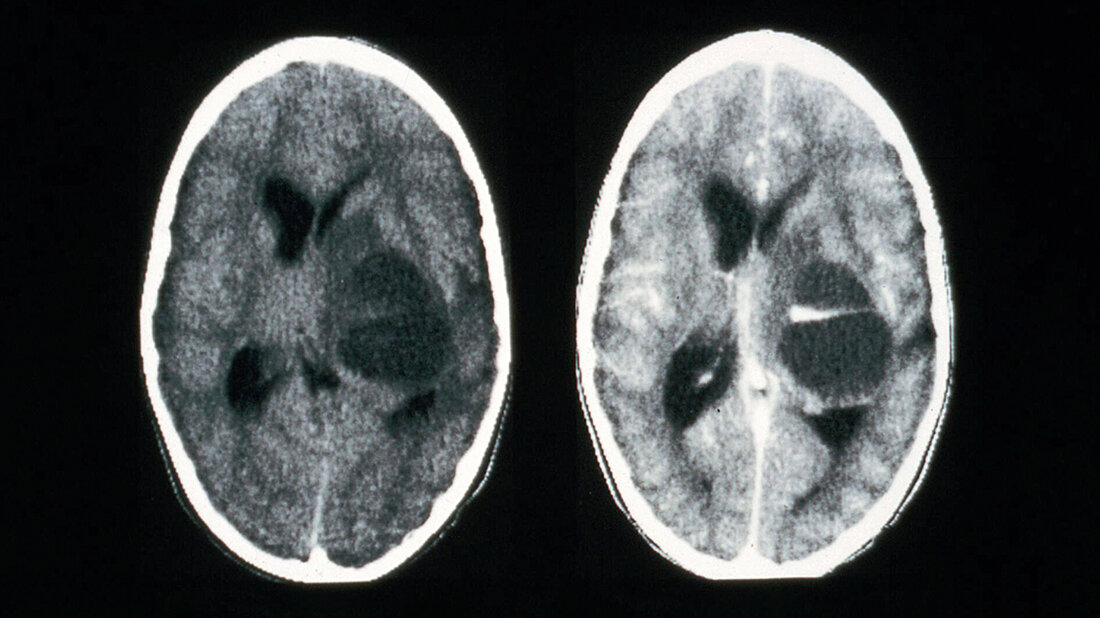

Radiological diagnosis of head injuries with a CT-Scan

Head CT scans are important for detecting brain diseases and diagnosing tumours. The images can help a doctor prepare for surgery. Usually, a head CT is used to provide an initial diagnosis. Another reason can be a check-up on how well a received treatment is working. Reasons that call for a head CT include: strokes, head injuries following accidents, skull fractures, brain tumours, cerebral haemorrhages, cerebral infarcts, vascular malformations, aneurysms or swelling of the brain.